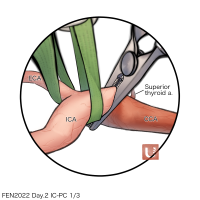

FEN2022シリーズ